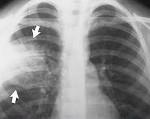

Полное диагностическое обследование при подозрении на внутрибольничную пневмонию строится на сочетании клинических, физикальных, инструментальных (рентгенография легких, КТ грудной клетки), лабораторных методов (ОАК, биохимический и газовый состав крови, бакпосев мокроты).

Для выставления соответствующего диагноза пульмонологи руководствуются рекомендуемыми критериями, включающими в себя: лихорадку выше 38,3°С, усиление бронхиальной секреции, гнойный характер мокроты или бронхиального секрета, кашель, тахипноэ, бронхиальное дыхание, влажные хрипы, инспираторную крепитацию. Факт внутрибольничной пневмонии подтверждается рентгенологическими признаками (появлением свежих инфильтратов в легочной ткани) и лабораторными данными (лейкоцитозом >12,0х109/л, палочкоядерным сдвигом >10%, артериальной гипоксемией Ра02

- Рентгенологического обследования органов грудной клетки в двух проекциях.

- Компьютерной томографии.